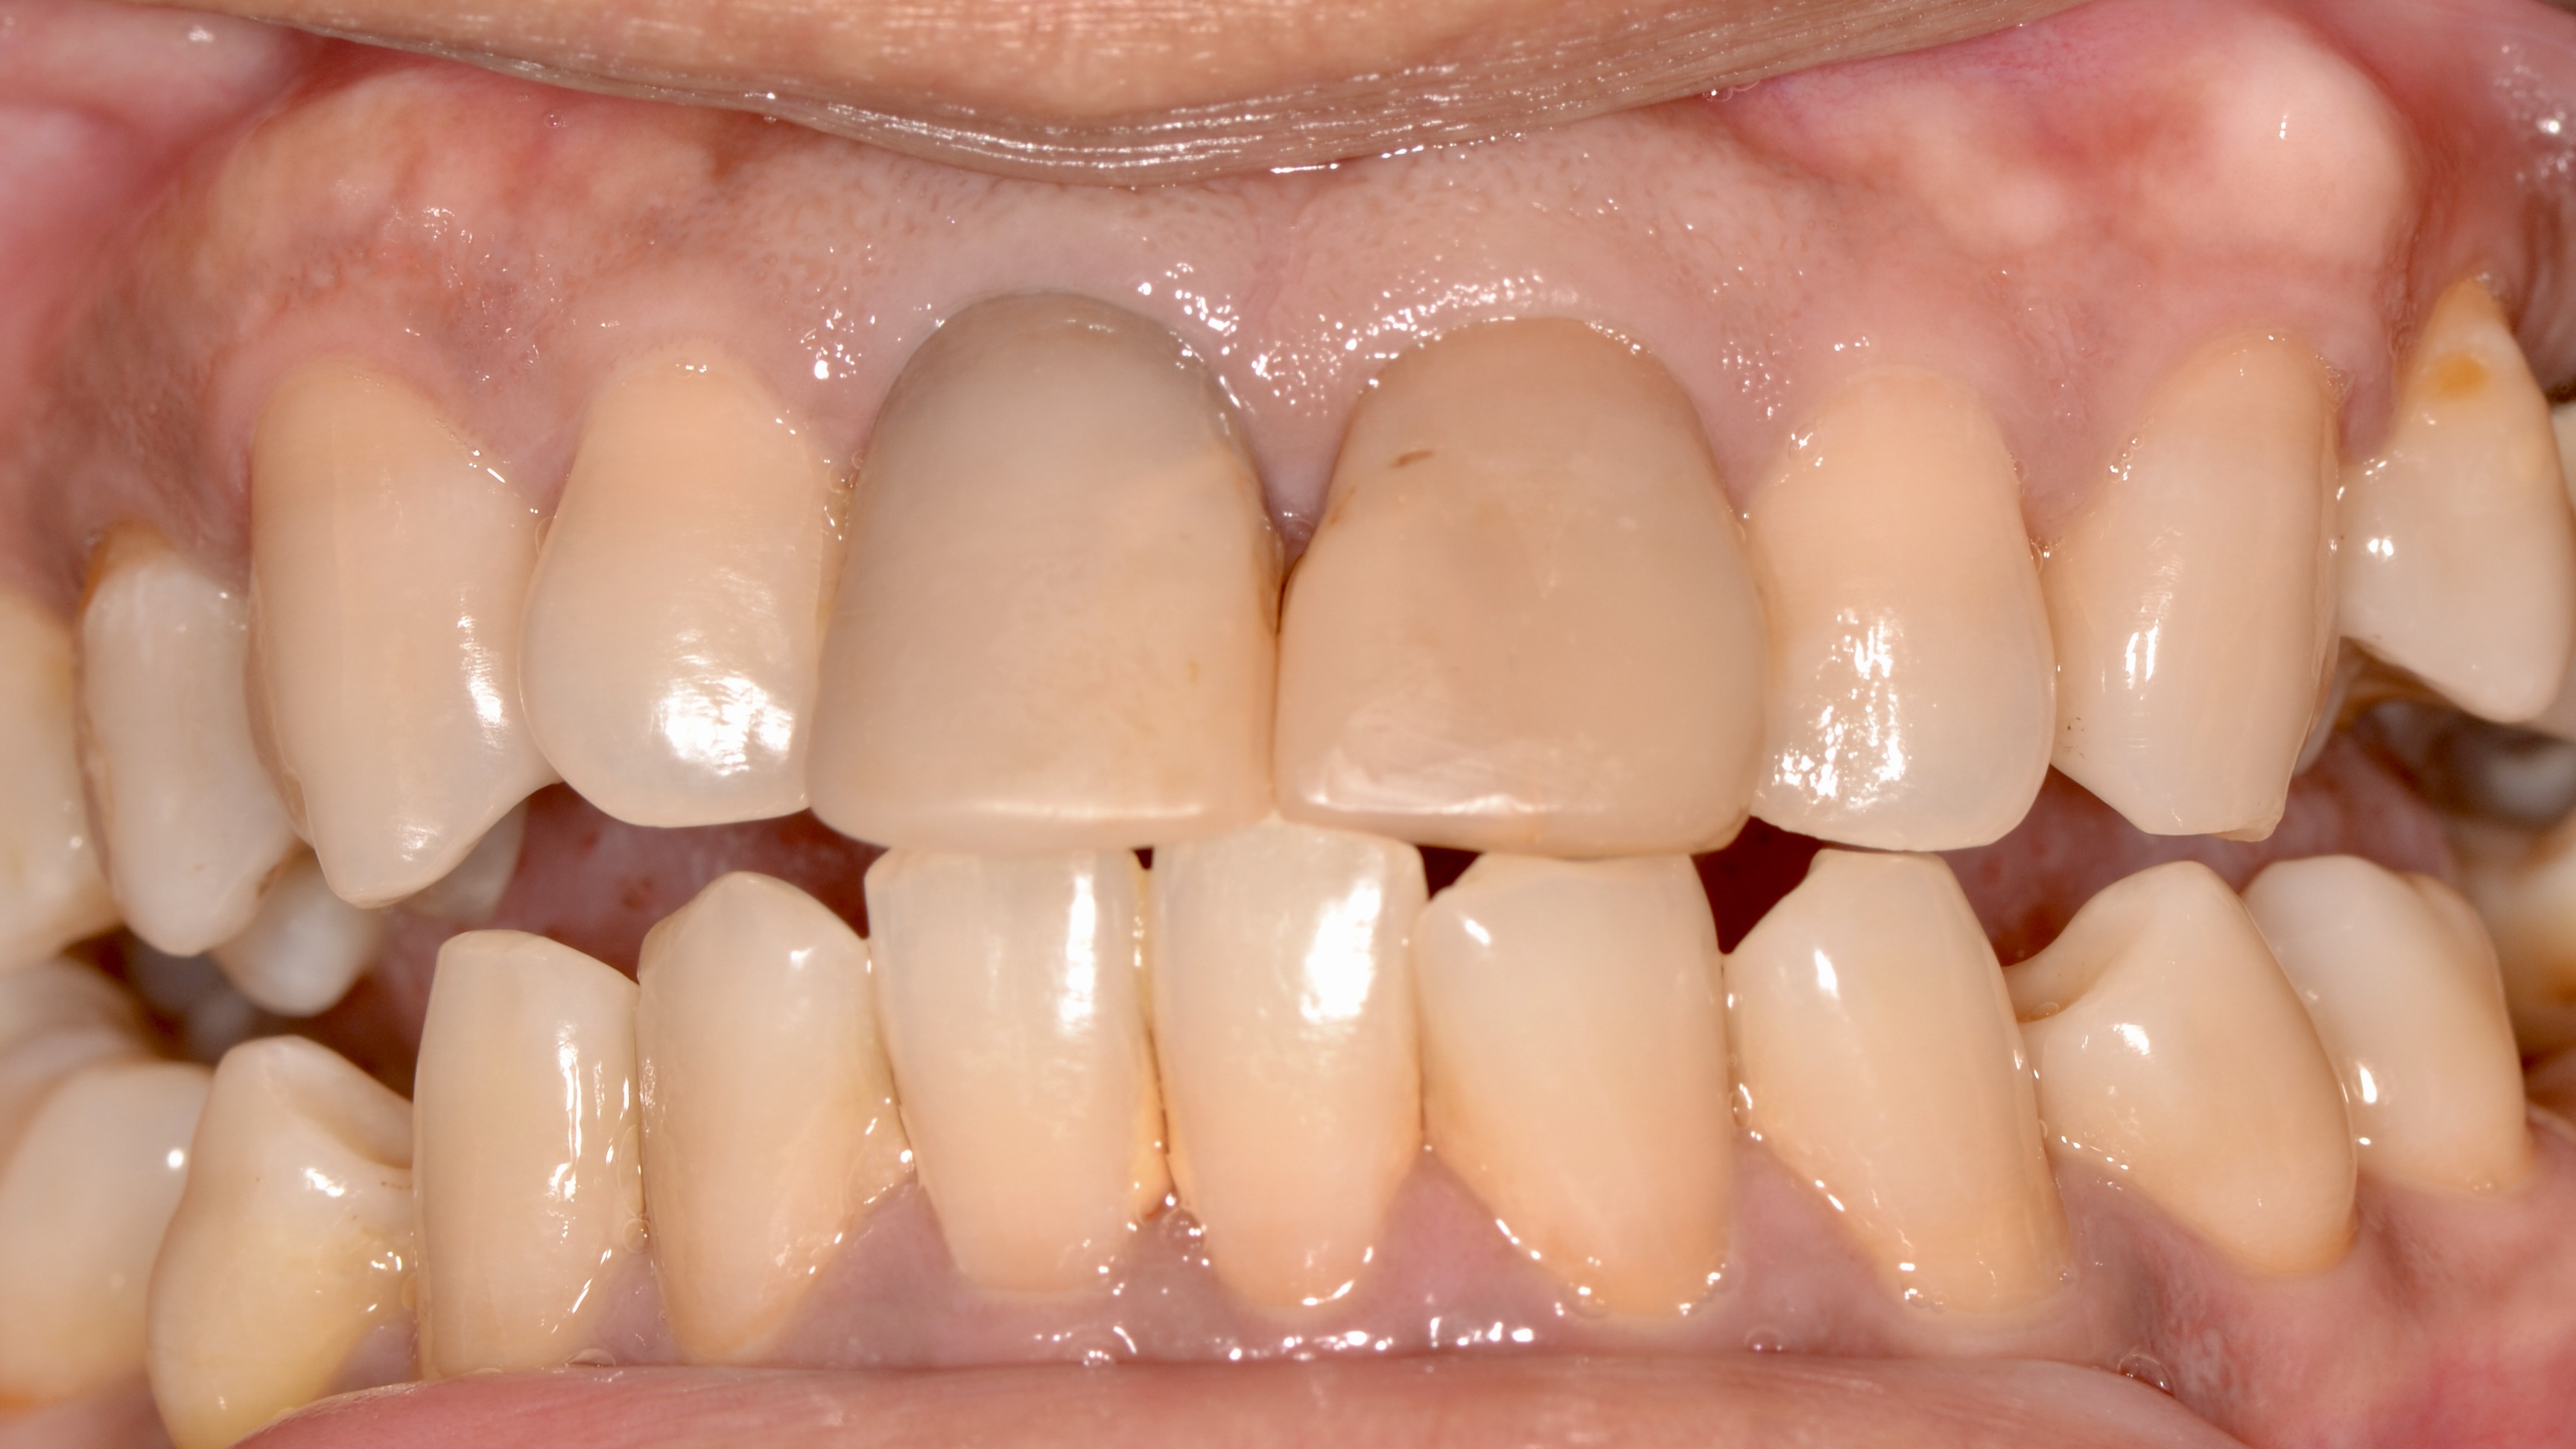

Composite Veneer